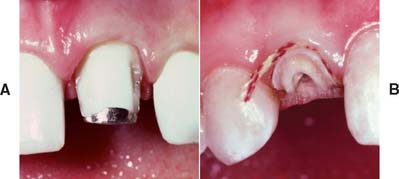

If the coronal structures are largely intact and loading is favorable, as on anterior teeth that are farther removed from the fulcrum (see Chapter 4), a simple filling can be placed in the access cavity (Fig. 12-2A). However, if a substantial amount of coronal structure is missing, a cast post and core is indicated instead (Fig. 12-2B). Molars are often restored with amalgam or a combination of one or more cemented posts and amalgam or composite resin (Fig. 12-2C and D).

Fig. 12-2 A, An anterior tooth with an intact clinical crown can be predictably restored with a composite restoration in the access cavity. B, When most coronal tissue is missing, a cast post and core is indicated to obtain optimal tooth preparation form. C, In mandibular molars, an amalgam foundation is retained by a cemented prefabricated post in the distal canal. D, In maxillary molars, the palatal canal is most often used.